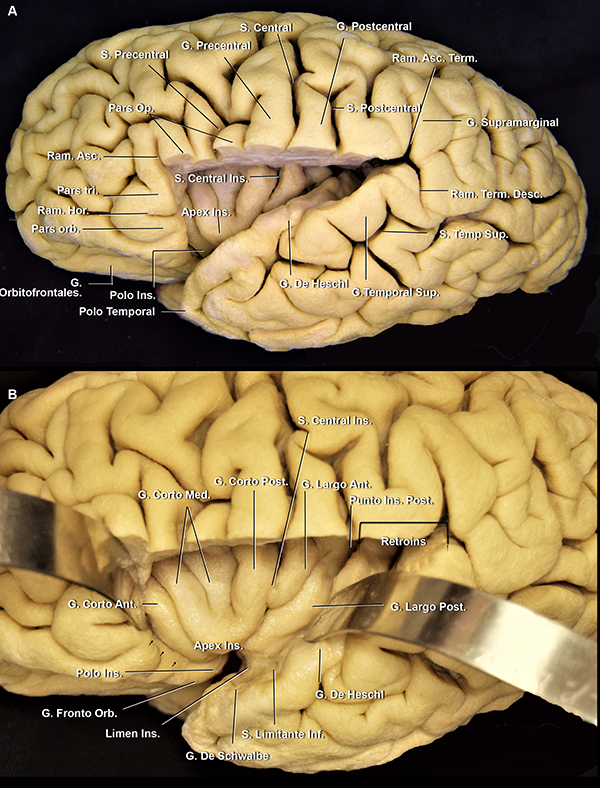

Figura 4: A. Vista latero inferior de un opérculo frontoparietal derecho. El opérculo temporal, la parte lateral del giro orbitario posterior y la parte posterior del giro orbitario lateral fueron removidas. Cuando el surco central no alcanza a la FS, el giro subcentral es visible en la cara lateral cerebral. En cambio, cuando sí lo hace, como en este caso, este giro se localiza en la profundidad de la fisura. Se observa cómo el ramo horizontal se continúa medialmente con el surco limitante anterior. El ápex insular se localiza superior y posteriormente al polo insular. B. Vista lateral del mismo espécimen. C. Vista de la superficie lateral de la ínsula de otro espécimen. Estrella azul: punto insular anterior. Estrella verde: punto insular posterior. S: surco; G: giro; Ant: anterior; Post: posterior; Op: opercularis; Ram: ramo; Hor: horizontal; Orb: orbitario; Ins: insular

El compartimiento opercular anterior se define como el espacio entre los giros orbitarios posterior y lateral y el plano polar del lóbulo temporal (Figura 5A y 6B). Por otro lado, la hendidura insular anterior se localiza entre la ínsula y los giros orbitarios lateral y posterior (Figura 1C,6B,7A).

Figura 6: A. vista lateral de un hemisferio cerebral izquierdo. Se removió el opérculo frontoparietal, preservando la pars orbitalis y triangularis. La punta de la pars triangularis se ubica superficialmente al ápex insular e inmediatamente posterior al polo y limen insular. B. Mismo espécimen. La superficie insular anterior enfrenta a los giros frontoorbitarios y el espacio estrecho entre estas estructuras es la hendidura insular anterior (flechas negras). La región retroinsular se extiende desde el extremo posterior de la ínsula al extremo posterior de la FS. S: surco; G: giro; Ins: insular; Sup: superior; Ram: ramo; Term: terminal; Asc: ascendente; Desc: descendente; Op: opercularis; Orb: orbitalis; Tri: triangularis; Hor: horizontal

Figura 7:A. vista lateral del lóbulo insular izquierdo del mismo espécimen que en la figura 1D y 9D. La superficie lateral de la ínsula está totalmente cubierta por M2 y sus ramas. El limen insular (círculo sombreado azul) limita la parte basal de la lateral de la FS y el segmento M1 de M2. Las arterias corticales tempranas no tienen un segmento insular dado que nacen del segmento M1 y pasan directamente al M3. B. Vista superior del mismo espécimen. El opérculo frontoparietal fue removido. C. Vista inferior de la ínsula del mismo espécimen. Los giros cortos tienen una dirección hacia el ápex insular. Debajo del ápex, la proyección inferior de los giros cortos se dirige hacia el polo insular. Los giros posteriores largos empiezan en el plano polar como un giro único que luego se divide en dos. S: surco; G: giro; Ant: anterior; post: posterior; Ins: insular; Acc: accesorio; Tran: transverso; Inf: inferior; Sup: superior; Orb: orbital; Hend: hendidura; Tempr: temprana.

Figura 9: A. Vista latero superior, quirúrgica, de una FS izquierda (mismo espécimen que en Figura 1B y C). Cabeza de flecha azul: limen insular. El limen insular se encuentra medial y anterior a la punta de la pars triangularis. A su vez, el polo insular se encuentra superolateral al limen insular y el ápex insular, superolateral al polo. Cuanto más posterior en la cisterna silviana, más profundo es el compartimiento opercular. Posterior al giro de Heschl, el opérculo temporal tiene una dirección recta en el plano axial, haciendo más dificultosa la apertura de la FS. B. Vista aumentada de A. C. Vista anterolateral de un hemisferio derecho. El opérculo frontoparietal fue removido. La bifurcación de la ACM se localiza proximal al limen insular (cabezas de flecha azul). D. Vista superolateral del mismo espécimen que en Figura 1D y 7. Las ramas corticales tempranas de la ACM pasan por el limen insular, así como los troncos postbifurcación. Ins: insular; G: giro; Bifur: bifurcación; S: surco; Orb: orbitalis; Fronto Orb: frontoorbitario; R: ramo; Tempr: temprano; Op: opercularis; Tri: triangularis; Pl: plano; Lim: limitante; inf: inferior.

El plano polar es un área integrada por giros cortos oblicuos menores: los giros de Schwalbe (Figura 6B).25 Por un lado, tiene una orientación lateromedial en el eje axial, escondiendo su punta anterior debajo del giro orbitario posterior (Figura 6).15 Por otro lado, tiene una orientación oblicua inferior en el eje coronal, que contribuye al agrandamiento del espacio subaracnoideo en el punto silviano anterior.22,23

El plano temporal está compuesto por dos o tres giros transversos. Es un área de forma triangular cuyo ápex apunta hacia el atrio ventricular. El giro de Heschl y la parte posterior del giro temporal superior constituyen el área auditiva primaria (Figura 6A, 10A y B).22 En su extremo anterolateral, el giro de Heschl se encuentra en el mismo plano coronal que el giro postcentral. Además, se evidenció que el giro de Heschl a su vez se encuentra en el mismo plano que el conducto auditivo externo (CAE) (Figura 5). En el plano coronal, tiene una orientación horizontal, haciendo que la disección de la fisura en esta área sea más dificultosa.